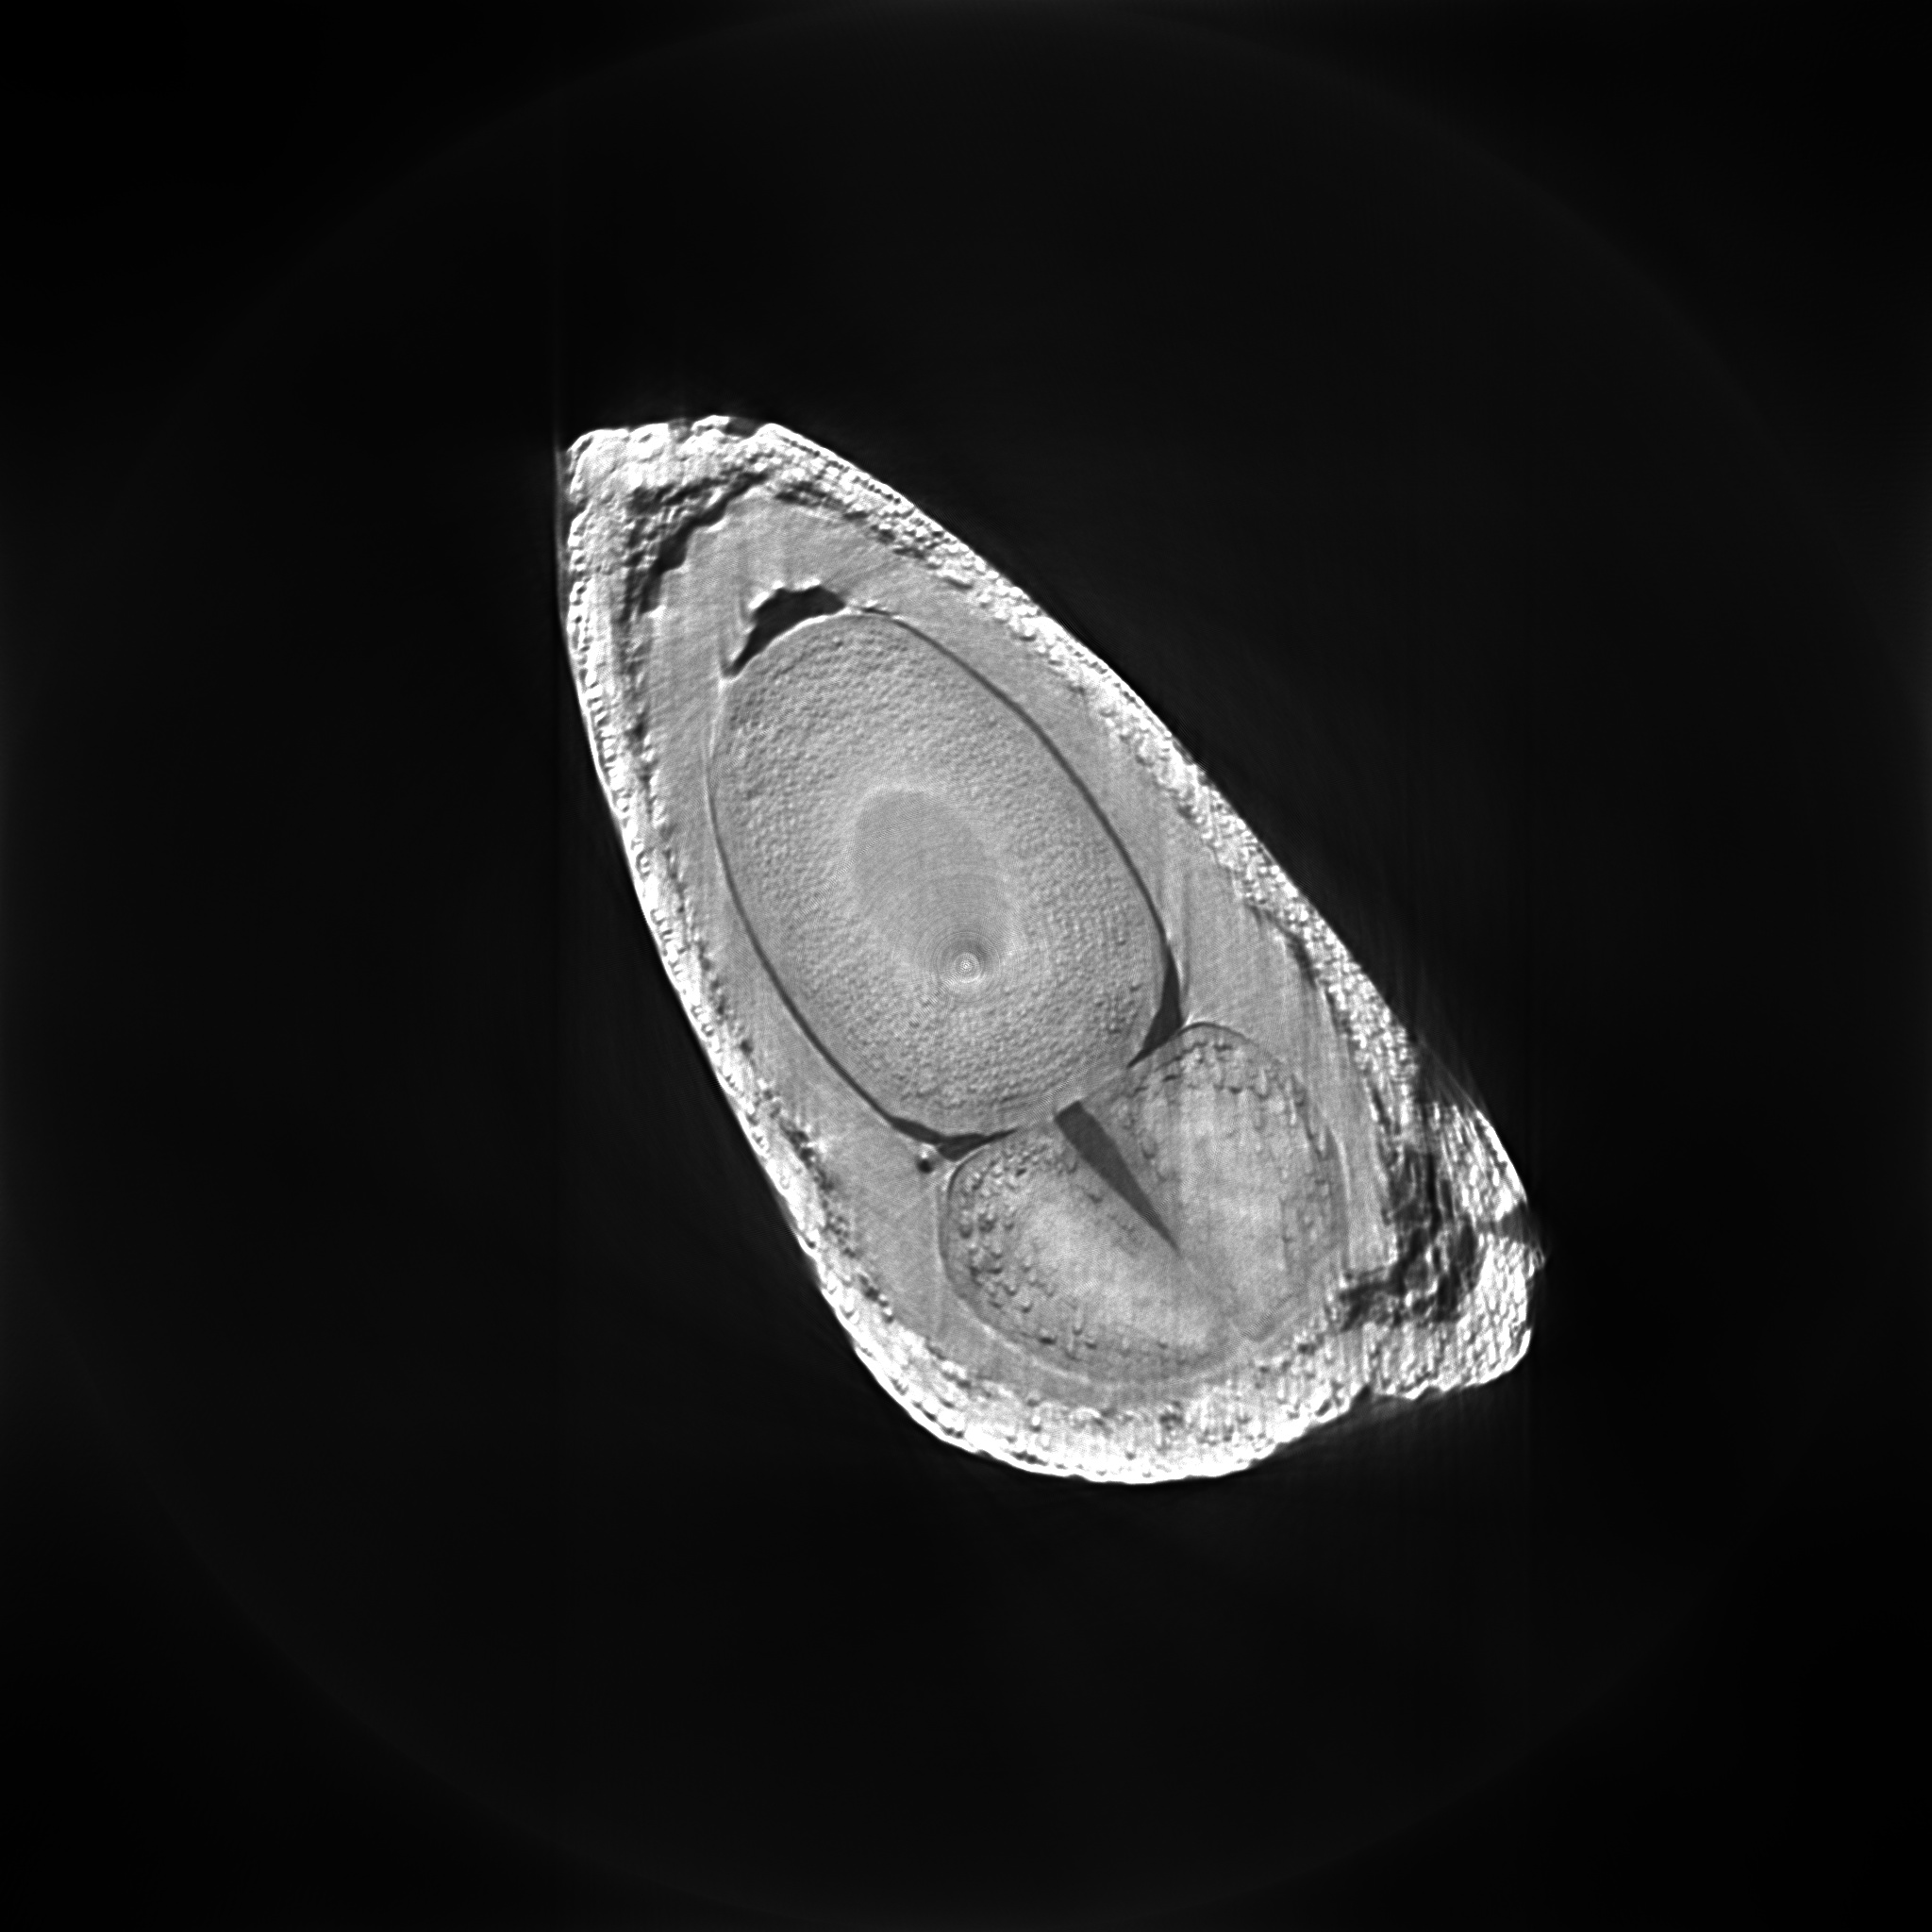

Tomographic setup

Data for this set of experiments was obtained at the Imaging Beamline (imx) of the Brazilian National Synchrotron Light Source (lnls) through illumination of an apple seed by x-rays. Each radiographic image was pixels in size and the sample was rotated by between each of the images, thereby totaling, for each slice to be reconstructed, views times rays of tomographic count data . Reconstructed images have dimensions of pixels.

Blank scans were measured before and after the actual tomographic measurements of the sample and then data was obtained by linear interpolation between these two measurements. This is necessary because because lnls is a 2 generation synchrotron that does not operate in a top-up mode, i.e., the storage ring is not injected periodically in order to maintain current constant. Therefore, flux is not constant and decrease exponentially with time. As this measurement was obtained with a short exposure time, we expect that ring current (hence flux) behaves approximately as a linear model. A 4 generation synchrotron source, such as the forthcoming brazilian source, Sirius, will operate in a top-up mode with more flux, i.e., samples will be measured with a short exposure time.

It is important to note that iterative methods such as those presented in this paper are extremely attractive for ultra-fast tomographic experiments, with an ultra-short exposure time and a considerable amount of noise. This is the case of soft-tissue samples where low dose should be considered and a analytical reconstruction method like filtered backprojection [11] produce low quality reconstructed images with strong streak artifacts.

The graphic on the right of Figure 5 displays plots of the objective function value versus total variation for the iterates of each method. The curves make clear that the superiorized version of the algorihtms always present the better compromise between data adhesion and smoothness when compared to its respective non-superiorized version. Figure 6 shows how this property translates to better image quality in practice. The lower row of Figure 6 shows isocontours overlaid on top of details of the images, in order to show that the superiorized image is noticeably smoother, therefore potentially more useful for visualization tasks. If, on the other hand, some apparent detail seems to have been removed from the image, part of these fine details may be reconstruction artifacts but we make no claims in this direction. Notice that these results are in accordance with those obtained using saem and its superiorized versions presented before.